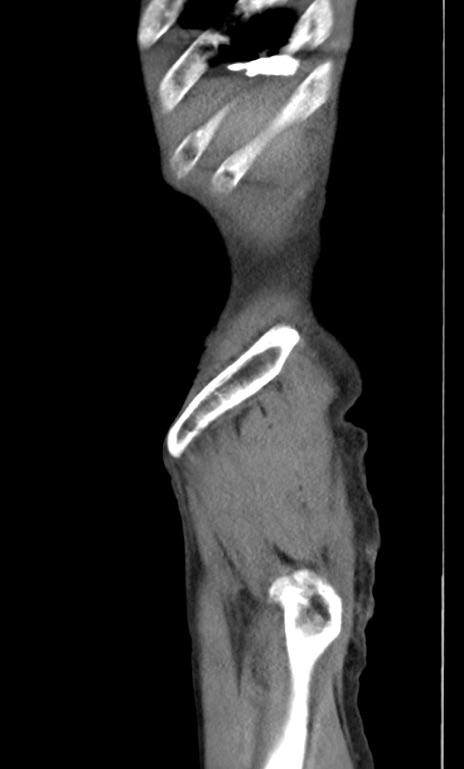

横断像

【症例】 70歳代男性

【主訴】右鼠径部腫瘤、疼痛

【現病歴】本日朝より上記主訴あり、受診。

【既往歴】膀胱癌にて膀胱全摘、両側尿管皮膚瘻

【データ】WBC 5600、CRP 0.56